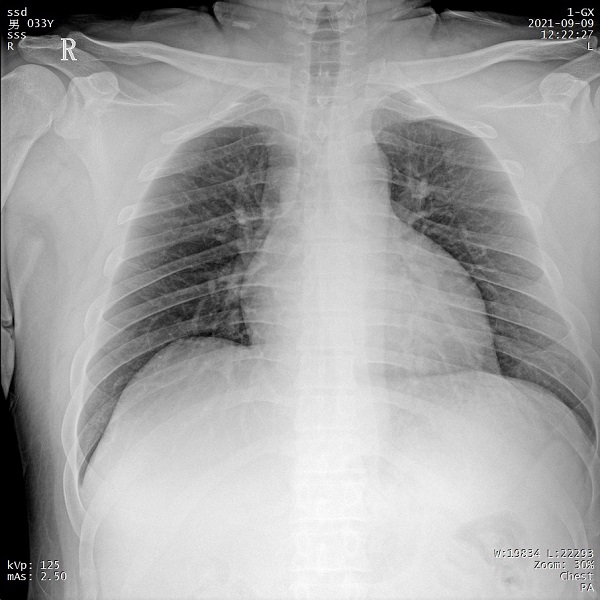

四、创伤患者可通过床旁摄影获取高质量图像

PLX5500凭借充沛的射线输出,能够在床旁对各体型创伤患者的各部位进行拍摄,输出清晰图像,辅助医生进行精确诊断。患者无需带伤前往放射科拍摄,降低二次伤害风险。